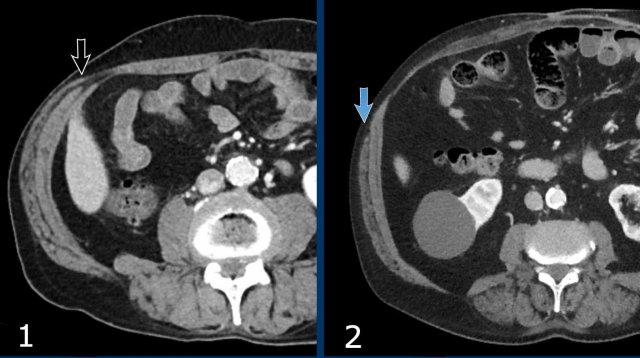

Các hình ảnh này thuộc về một bệnh nhân nữ 78 tuổi, béo phì nặng, có thoát vị thành bụng đường giữa sau phẫu thuật.

Hãy nghiên cứu các hình ảnh này, sau đó so sánh với các hình ảnh tiếp theo được chụp một tháng sau, khi bệnh nhân nhập viện với khối thoát vị sưng đau.

Hiện tại đã xuất hiện các dấu hiệu của thắt nghẹt, cụ thể là:

- Dấu hiệu phân trong ruột non mới xuất hiện, thấy rõ nhất trên các lát cắt ngang (mũi tên trắng).

- Thâm nhiễm mỡ mạc treo (mũi tên đen).